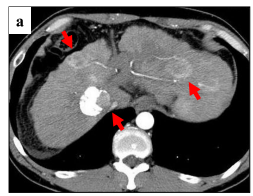

患者男性,69,工人。 患者2020-01-31因“贲门癌”和“肝癌”在我院行“全胃切除伴食管空肠Y型吻合术+左半肝切除术+解剖性肝段切除术”。术中见左肝内叶触及...